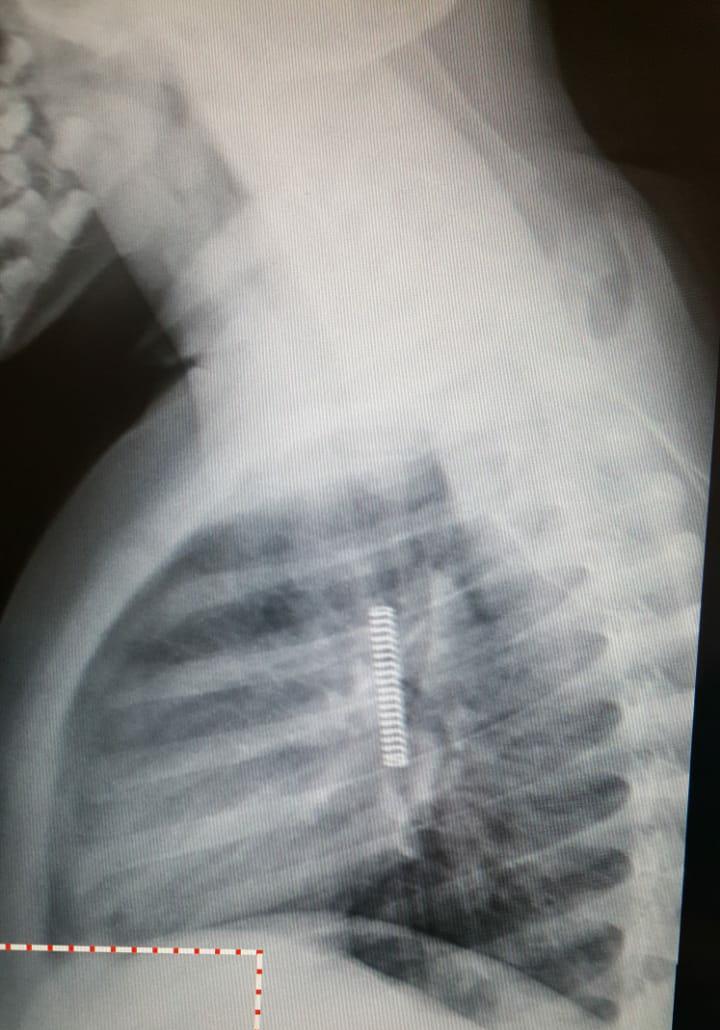

La operación de Francesco salió bien pero aún se encuentra internado en el Juan XXIII de Roca. Esta mañana, el niño de 6 años años fue intervenido quirúrgicamente porque desde el domingo tenía un resorte de siete centímetros en la zona de los pulmones.

Según contó su mamá Estefania, el domingo por la tarde mientras jugaba en su casa en Fernández Oro se tragó el objeto metálico. “Al ser en espiral podía respirar, pero yo me asusté mucho, los médicos me dijeron que fue un milagro”, contó.

El niño fue asistido en Fernández Oro pero rápidamente fue derivado a Cipolletti. Allí, le dijeron a la mujer que era posible que lo pueda expulsar pero que si eso no ocurría podía tener serias complicaciones. En las imágenes de las placas se ve claramente el objeto en la zona de los pulmones. Finalmente decidieron trasladaron al Juan XXII, el domingo a la noche.

Una de las placas que le tomaron en el hospital de Cipolletti.